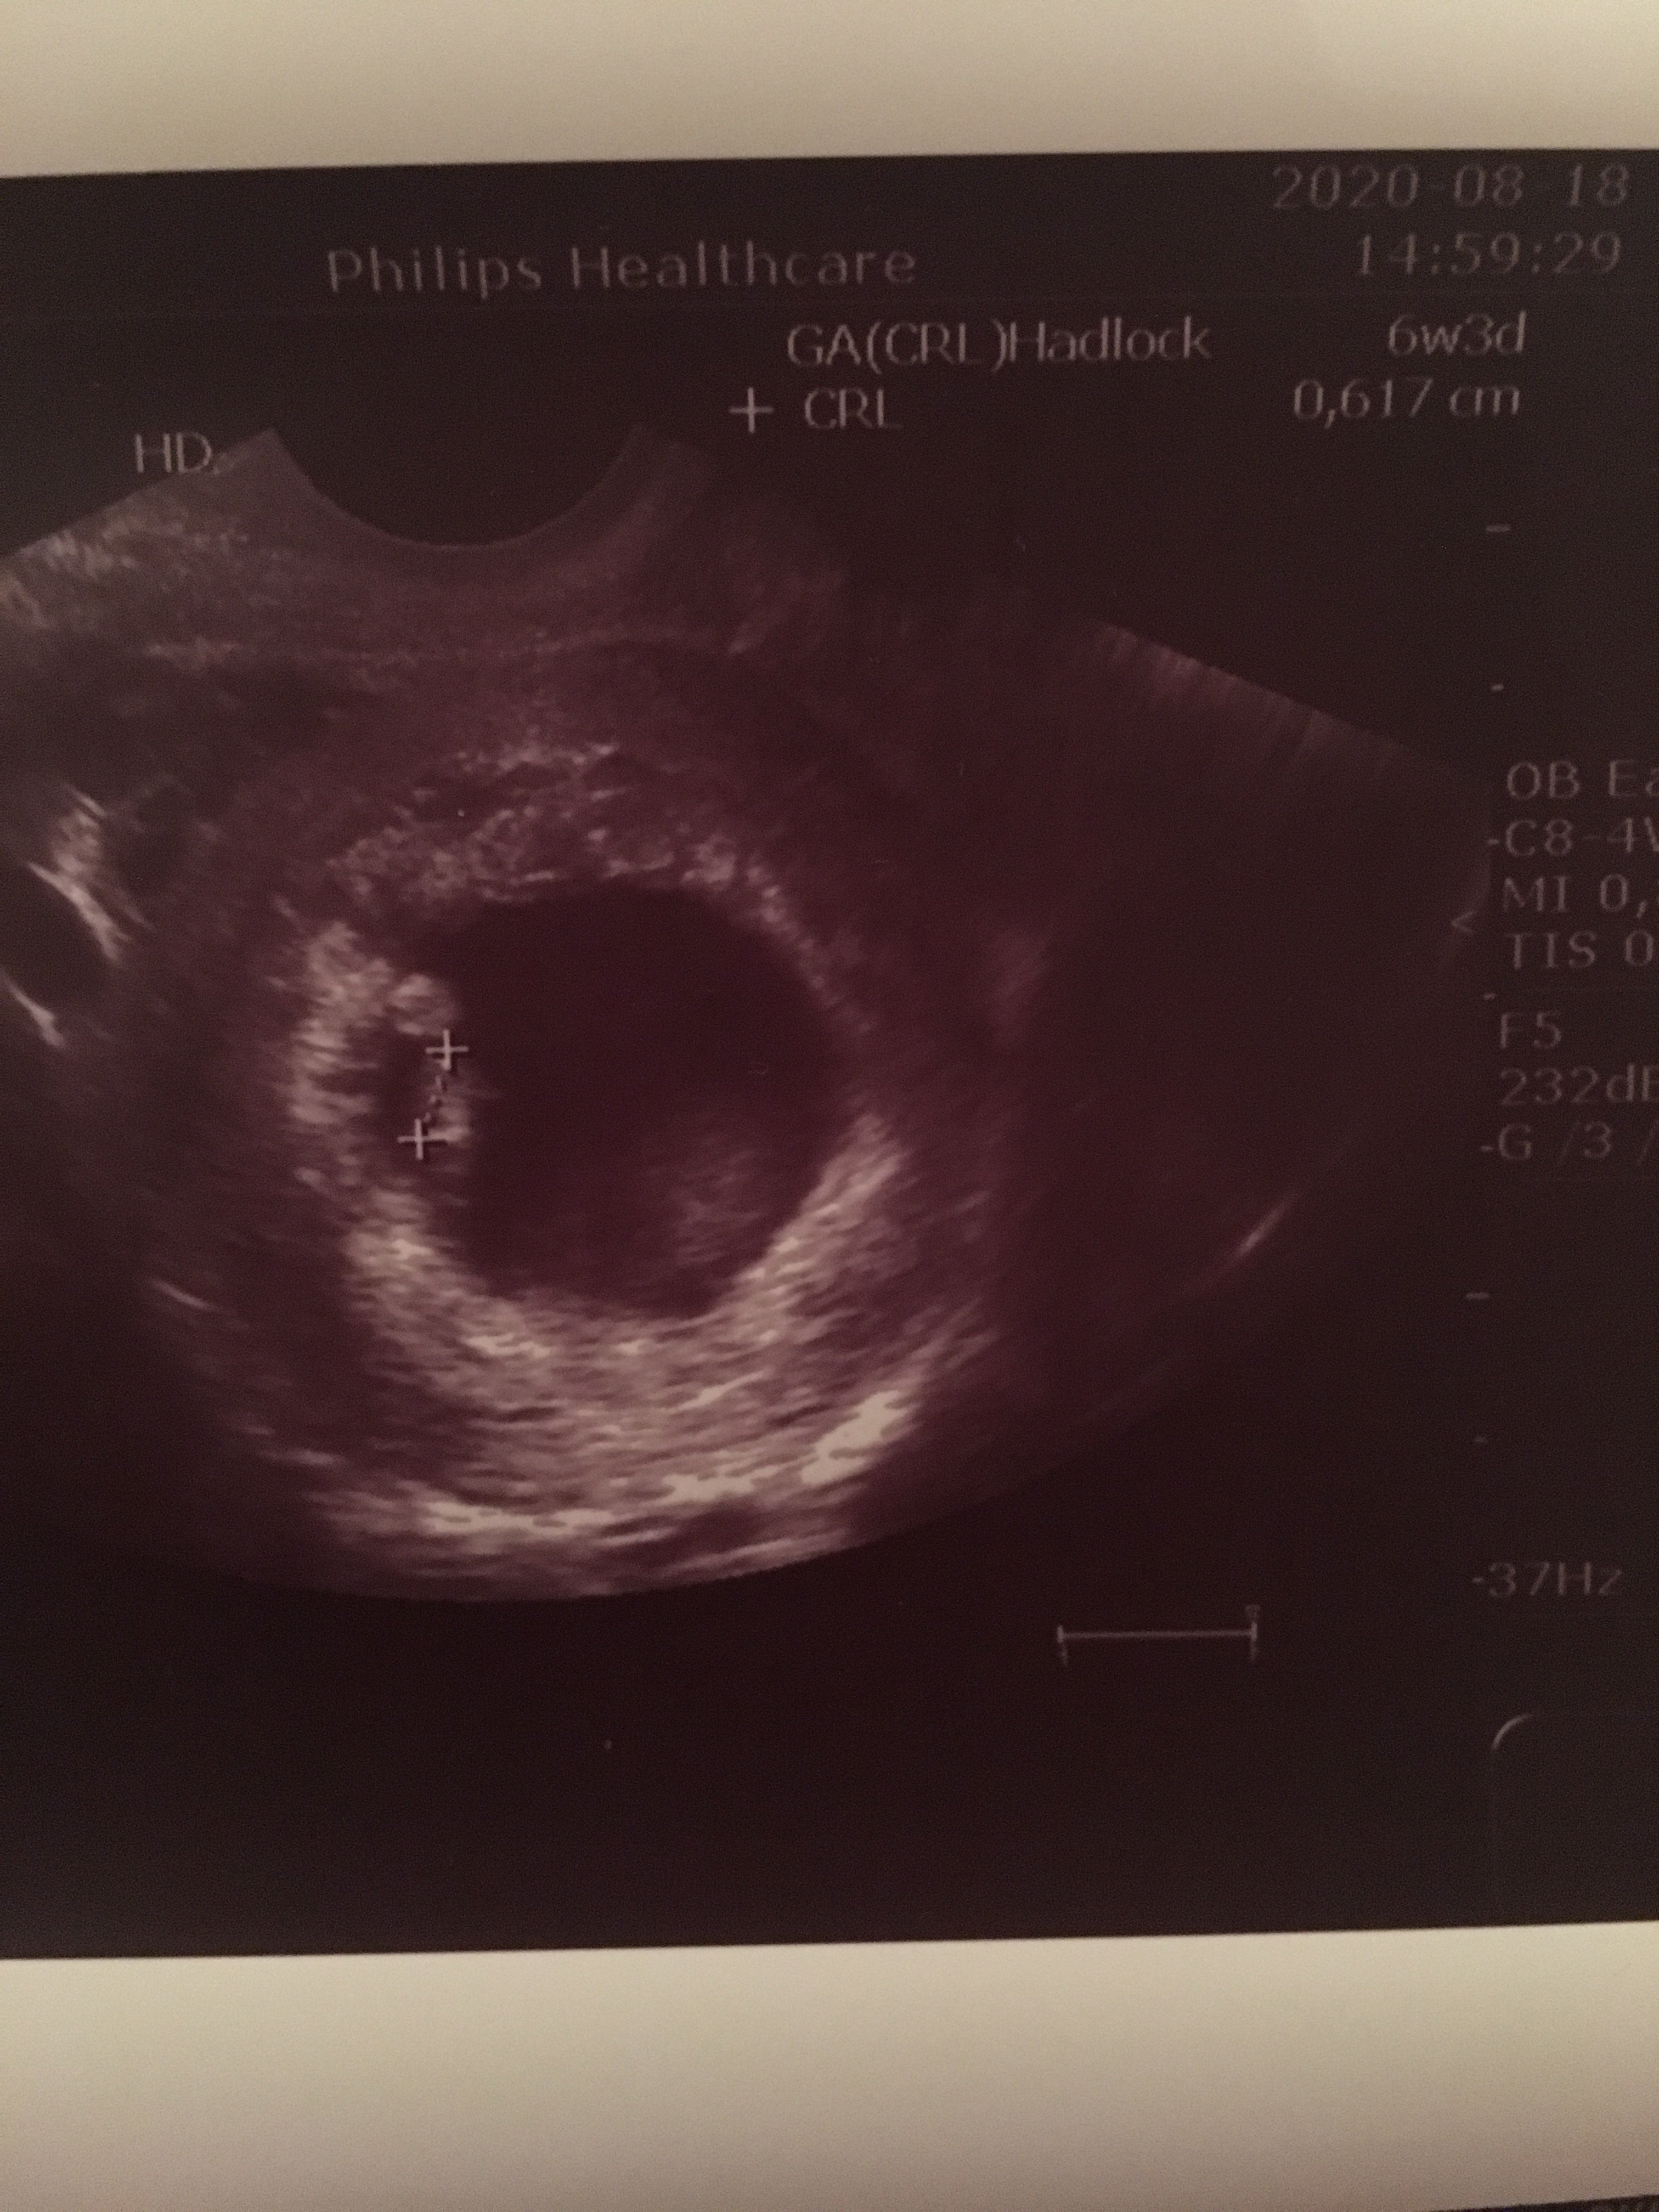

No aż zdjęcie z usg wyciągnęłam:

Mój wczoraj, czyli w 6+2 miał 5,5 mm6 ale nie cm tylko mmpomyłka przy czytaniu, bo aż wróciłam do swojej wiadomości żeby się upewnić ze babola nie zrobiłam

No aż zdjęcie z usg wyciągnęłam: Zobacz załącznik 1165336

U mnie dzisiaj 5 mm, a mam 6+1

Mój wczoraj, czyli w 6+2 miał 5,5 mm[emoji6]